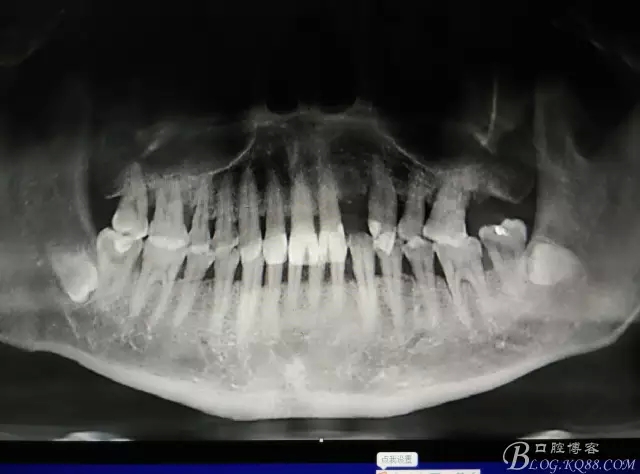

患者、楊xx、男、49歲。主訴:左側(cè)前牙拔除半年,活動義齒修復(fù)四個(gè)月,要求種植修復(fù)。??茩z查:21缺失,牙槽粘膜厚度正常。CBCT檢查:高度16mm,寬度7mm.術(shù)前簽知情同意書。

圖1.術(shù)前的CBCT檢查:22缺失。